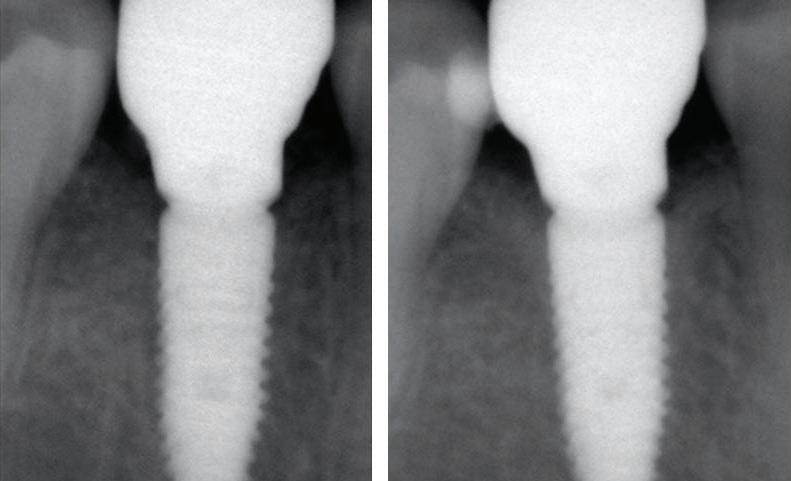

Figure 1: Radiographic Image of implants do not demonstrate bone loss due to the bisecting angle of the radiograph taken.

Figure 2: Radiographic image in a paralleling technique of implants dem onstrate moderate peri-implantitis with bone loss that will necessitate treatment.